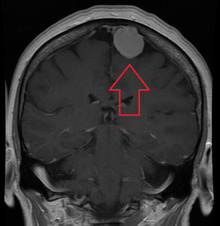

Meningiomas are visualized readily with contrast CT, MRI with gadolinium,[17] and arteriography, all attributed to the fact that meningiomas are extra-axial and vascularized. CSF protein levels are usually found to be elevated when lumbar puncture is used to obtain spinal fluid.